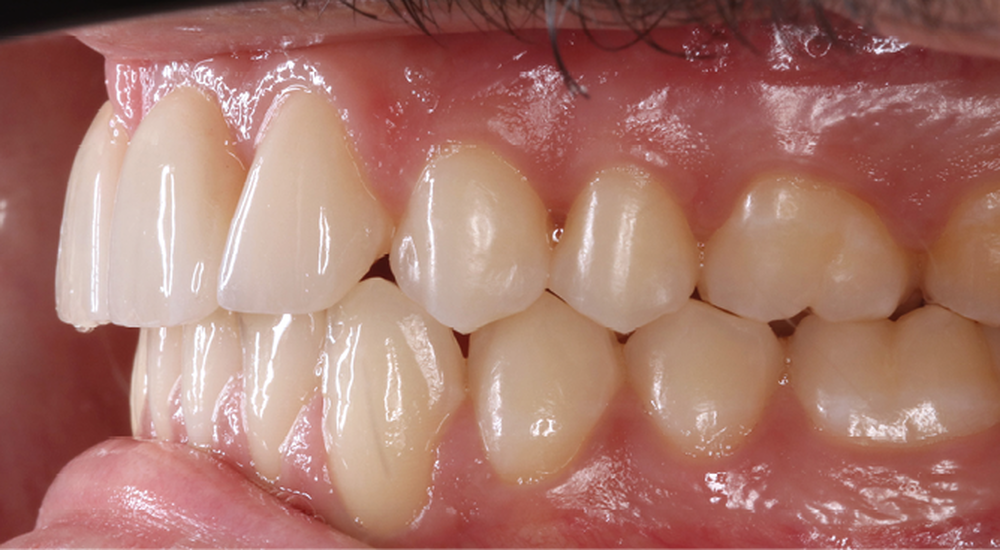

Antony, 11 ans se présente initialement pour une demande esthétique concernant ses deux incisives centrales qu’il trouve trop grosses (fig. 1a-c).

Le profil est convexe et associé à une inocclusion labiale au repos. Il s’agit d’une classe II squelettique sur un schéma facial normodivergent. Les rapports occlusaux sont de classe II bilatérale (complète au niveau molaire) avec des incisives inférieures vestibulo-versées. La 21 est géminée et la 11 vraisemblablement fusionnée avec un germe surnuméraire, sans altération de la formule dentaire. Du fait du diamètre mésiodistal fortement augmenté des incisives centrales, et du manque de place à l’arcade maxillaire qui en découle, les 12 et 22 sont en inversé d’occlusion en palato position. Les 53 et 63 sont persistantes sur l’arcade avec une inclusion en transposition incomplète de la 13, dont la cuspide se situe entre la racine de la 12 et celle de la 11 résorbée (fig. 1d-g).